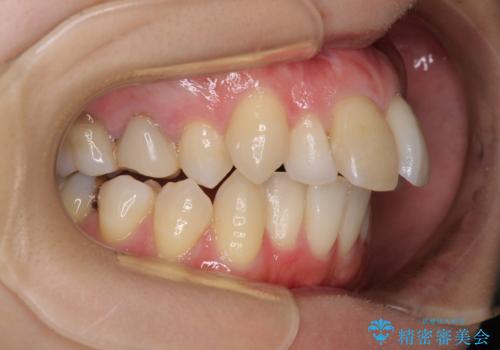

- 口を閉じたときに飛び出してしまう上顎前歯を気にして来院された患者様です。

上下の咬み合わせは上顎歯列全体が歯1本分前にずれている状態であり、さらに上顎歯列はV字型に尖っていたため、上下前歯は全く接触していない状態でした。